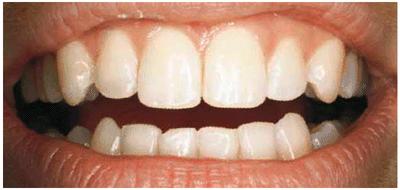

smile (Figur 323s1823d es 18-1A, and 18-1B). Decades ago, the full crown

Figur 323s1823d e 18-1A: This 21-year-old girl had chipped her anterior incisors when she was a teenager.

Figur 323s1823d e 18-1B: Cosmetic contouring was the most conservative treatment available and was performed in a less than 1-hour appointment.